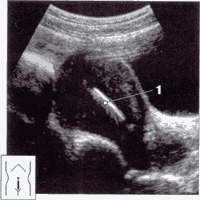

При внематочной беременности и для определения уровня хорионического гонадотропина, УЗИ – это один из основных методов выявления этой патологии.

Под контролем УЗИ сейчас проводят инвазивные манипуляции: пункцию брюшной полости и различных образований в полости малого таза; лечат внематочную беременность; пункцию фолликулов во время лечения бесплодия методом ЭКО; селективную редукцию эмбрионов при многоплодной беременности; амниоцентез и биопсию хориона для диагностирования врожденных пороков и болезней плода и иное.